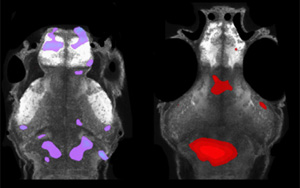

Science子刊:世界首個(gè)能抵御致死性細(xì)菌感染的mRNA疫苗問(wèn)世

近日,一篇發(fā)表在國(guó)際雜志Science Advances上題為“A single-dose F1-based mRNA-LNP vaccine provides protection against the lethal plague bacterium”的研究報(bào)告中,來(lái)自以色列特拉維夫大學(xué)等機(jī)構(gòu)的科學(xué)家們通過(guò)研究開發(fā)出了首個(gè)基于mRNA的疫苗,其或能100%有效抵御一種對(duì)人類致死的細(xì)菌。